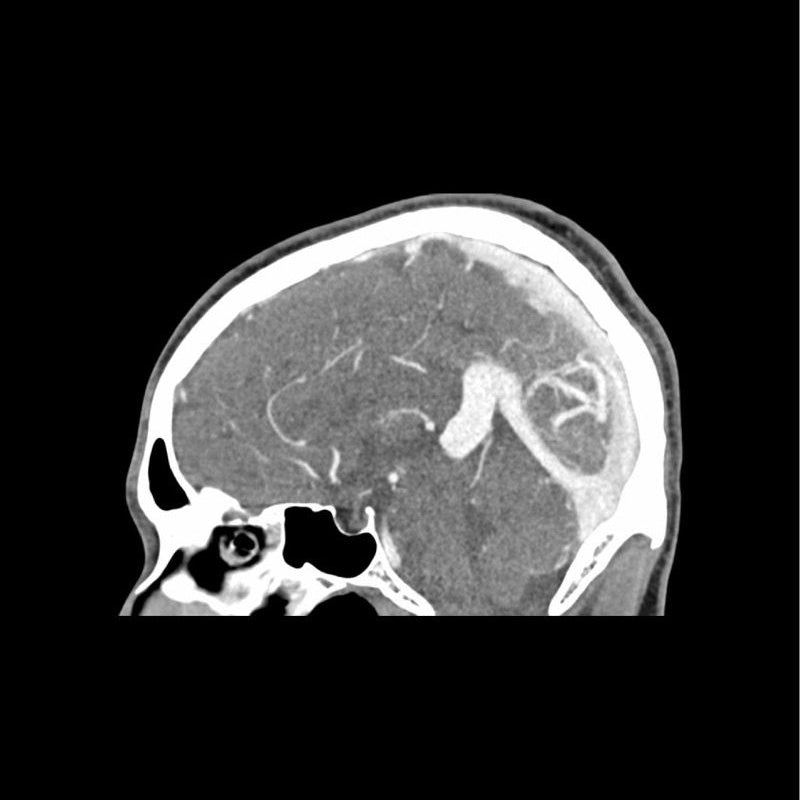

This phantom simulates a contrast medium enhanced head in arterial phase (CT angiography). It covers the vertex to the foramen magnum. The phantom has 10 low-contrast lesions in the centrum semiovale and the right hemisphere has an arteriovenous malformation.

The phantom can be used in CT (including CBCT) to evaluate and optimize imaging performance and AI-enabled diagnosis. It is also suited for training purposes. The phantom provides a detailed and realistic simulation of vascular structures, soft and bone tissue. Air voids are filled with a cellulose-polymer composite of approx. -160 HU.

- Realistic simulation of head vessels, bone and soft tissues.

- Arteriovenous malformation of the right hemisphere.